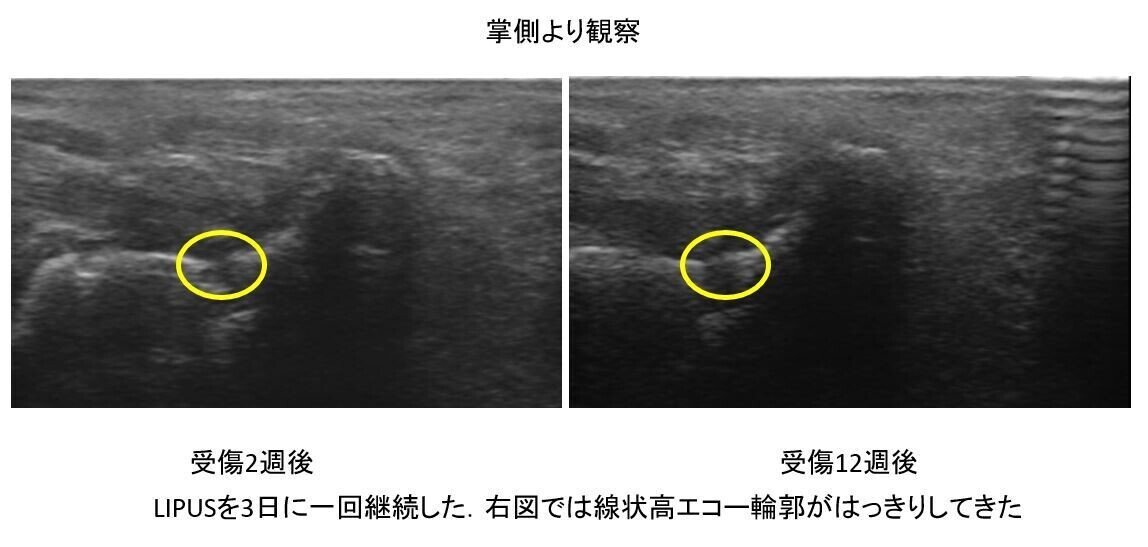

その後はサムスピカ型プライトンシーネ固定

そしてLIPUSを施行しました

4週もすれば疼痛は軽減し

スナッフボックスの圧痛も減少してきました

患者も疼痛が減少してきたら

固定にわずらわしさを感じてきます

そのため

必ずエコーで経過を一緒に観察しながら

アドヒアランスを得て

固定のレベル・強度を調節していきましょう

ここではよく観察できる

掌側走査 短軸のみのご紹介となりました